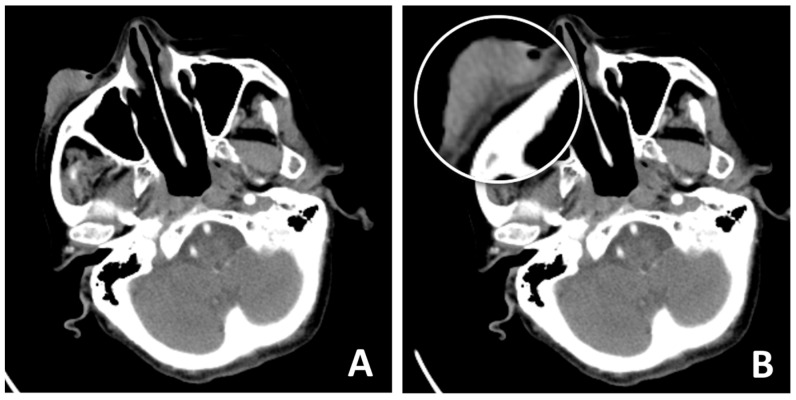

Background: Restoring the integrity of the lower eyelid presents a complex surgical challenge due to its lamellar structure and the high risk of complications. Among these, ectropion is the most frequent and troublesome outcome. Objective: This study aims to present a case of lower eyelid reconstruction following the excision of squamous cell carcinoma using Mohs micrographic surgery combined with the Mustardé cheek rotation flap technique, highlighting its advantages, limitations, and applicability in elderly patients. Case presentation: A 93-year-old female patient with right lower eyelid squamous cell carcinoma underwent Mohs micrographic surgery. The resulting defect was reconstructed using a Mustardé cheek rotation flap, chosen for its suitability in patients with adequate skin laxity. Patient-specific risk factors, including advanced age, a history of ischemic stroke, and class II heart failure (NYHA classification), were considered in the surgical planning stage. Results: The Mustardé cheek rotation flap provided a reliable closure with a favorable esthetic outcome and inconspicuous scarring, aligned with natural anatomical margins. The technique was technically straightforward in this patient owing to age-related skin laxity. No major postoperative complications were observed. Conclusions: The Mustardé cheek rotation flap represents a safe and effective reconstructive option for elderly patients with lower eyelid defects following tumor excision. This case illustrates the esthetic and functional benefits of the technique while emphasizing the need to tailor reconstruction strategies to patient comorbidities and defect characteristics.